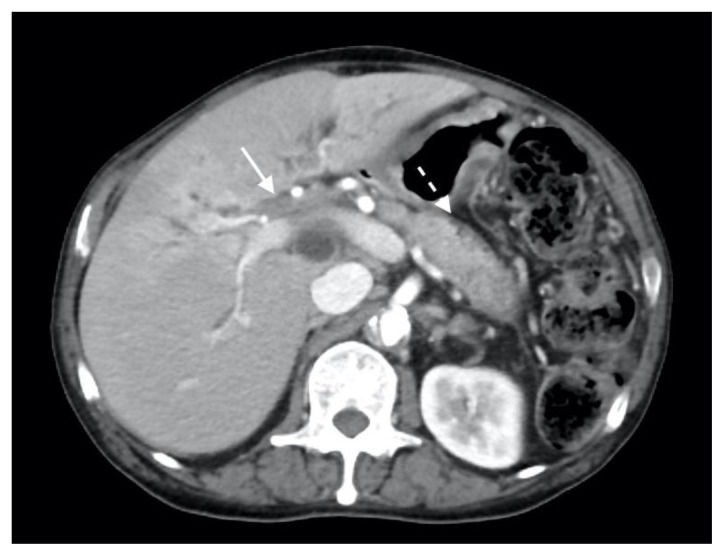

The patient next underwent contrast enhanced computed tomography (CT) of the abdomen and pelvis, which revealed infiltrative soft tissue in the region of the biliary hilum with moderate to severe upstream intrahepatic biliary dilatation, suggestive of a stricture (Figure 1). There was heterogenous enhancement throughout the liver, with a focal hypoenhancing region noted in the left hepatic lobe (Figure 2). It was unclear if this focal lesion represented a hepatic mass, pseudotumor or inflamed parenchyma. The pancreas had lost its normal lobulated architecture and its parenchyma was diffusely enhancing with a surrounding rind of soft tissue (Figure 1). These findings were suggestive of autoimmune pancreatitis. Soft tissue also surrounded the proximal aspects of the superior and inferior mesenteric arteries (Figures 3, 4). Asymmetric prominence of the seminal vesicle was also noted, thought to be due to an underlying prostatic lesion or an infectious or inflammatory prostatitis.

Figure 1.

78 year-old male with IgG4-related autoimmune disease.

Findings: Axial contrast-enhanced CT demonstrates enhancing soft tissue in the biliary hilum (solid arrow) and loss of pancreatic parenchymal lobulations with a peripancreatic soft tissue rind (dashed arrow).

Technique: Axial Multi-detector CT, Portal Venous phase (100 ml Omnipaque), mA 50–200; kV 120; 5.0 mm slice thickness.